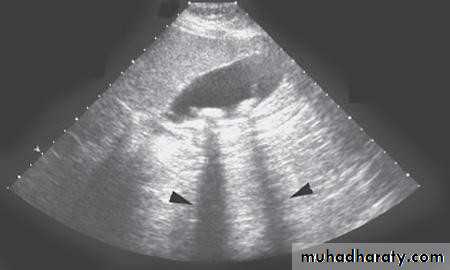

•  Ultrasonography:

•  Non-invasive

•  Standard initial imaging for patient suspected to

• have a gall stone and in jaundiced patients.

•  Ultrasonography:can demonstrate

•  Gall stones

•  GB size, thickness of its wall, presence of inflammation around it, pericystic edema.

•  Size of CBD, occasionally stones in it.

• DIAGNOSIS

•  Ultrasound